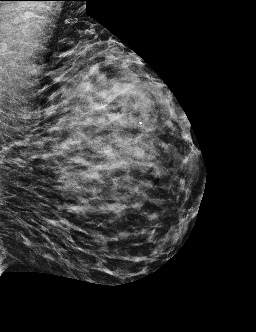

15 Per-channel Input Examples

Fig. 11 shows samples of per-channel inputs for the mid-resolution and high-resolution models in the MAMBO pipeline.